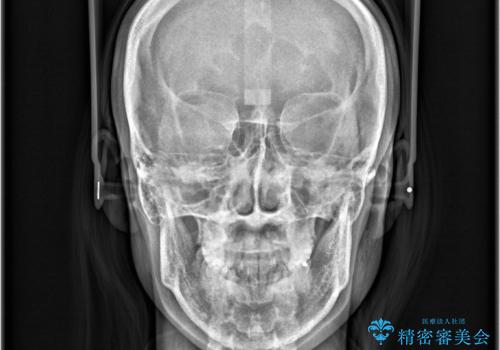

- 「歯のデコボコと前歯が出ているせいで口が閉じにくい」を主訴に来院された患者様です。

上下左右の4番(第一小臼歯)を抜歯をし審美ワイヤー装置で治療を行いました。

抜歯矯正により歯列のデコボコ(叢生)が改善し、前歯の突出も解消されたことで口元が下がり、すっきりとした印象となりました。